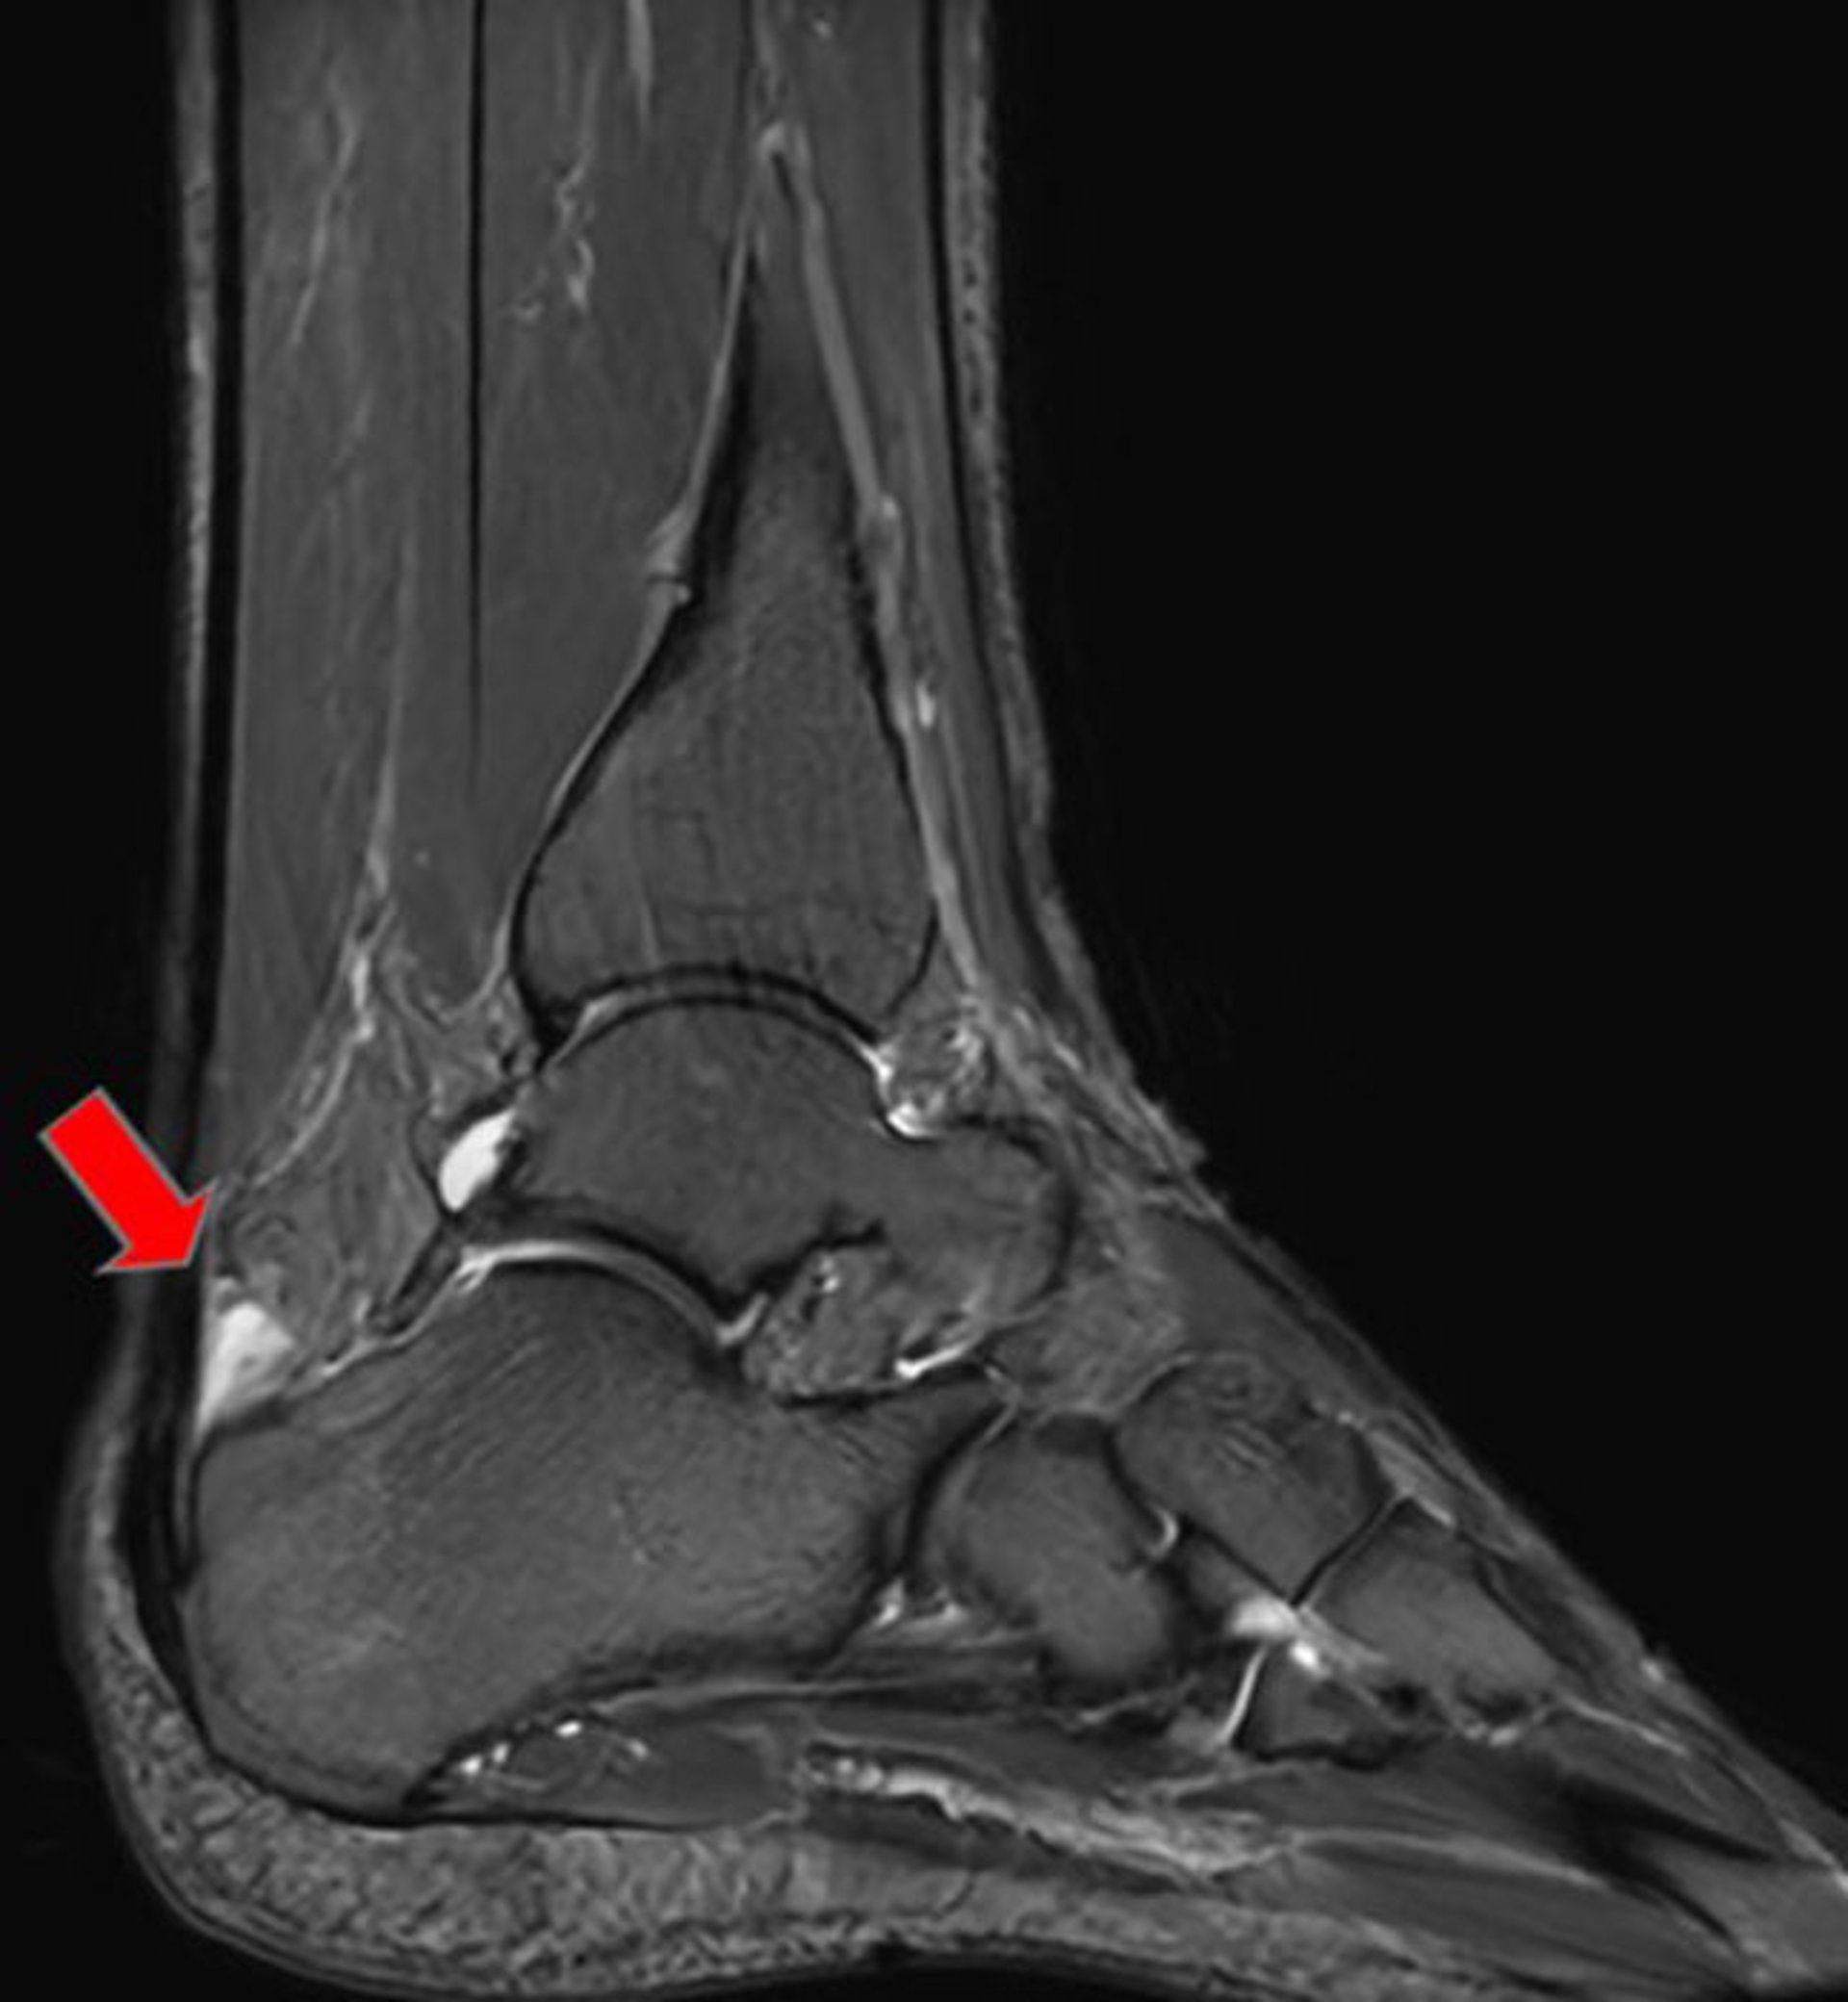

Os trigonum syndrome commonly presents with posterior ankle pain that can mimic symptoms of Achilles tendon disorders such as retrocalcaneal bursitis. It is the result of a partial or incompletely fused accessory ossicle located adjacent to the flexor hallucis longus (FHL) tendon as it crosses the subtalar joint at the posterior aspect of the talus and superior to the calcaneus. The presence of an os trigonum does not always equate to a painful syndrome. However, in patients who develop posterior ankle pain in the setting of repetitive stress related to hallux plantarflexion (eg, a ballerina dancing "en pointe" or in forced ankle plantarflexion), os trigonum syndrome should be considered.

Findings on MRI include signal intensity at the ossicle as well as the adjacent part of the FHL tendon.

Radiographs are taken to exclude fracture and to reveal erosive calcaneal changes characteristic of chronic rheumatoid arthritis, gout, or spondyloarthropathies. Magnetic resonance imaging (MRI) of the Achilles tendon can confirm the presence of bursitis and exclude alternative diagnoses such as partial or full tendon rupture as well as calcaneal stress fracture. MRI is also helpful to distinguish between a posterior talar process fracture and os trigonum syndrome.